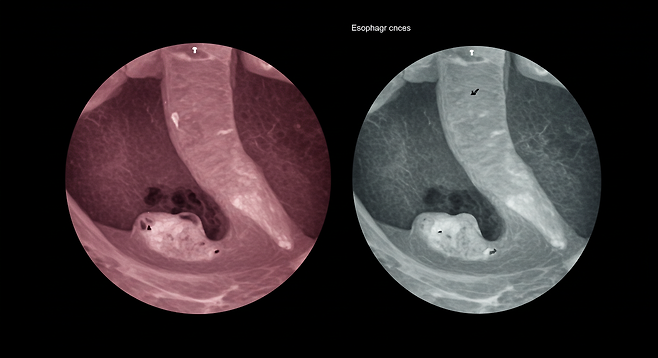

식도암이란?

식도암은 입과 위를 연결하는 식도에 발생하는 악성 종양입니다. 식도의 내벽을 구성하는 세포에서 주로 발생하며, 편평세포암과 샘암종이 가장 흔한 유형입니다. 우리나라에서는 편평세포암이 전체 식도암의 약 95%를 차지하고 있으며, 주로 60대 이상 남성에게서 많이 발생합니다.

식도암은 초기에 발견하면 5년 생존율이 90% 이상으로 완치 가능성이 높습니다. 그러나 증상이 나타난 후 발견된 경우에는 이미 진행된 상태일 가능성이 높아 예후가 좋지 않을 수 있습니다.식도암 초기 발견을 위해서는 정기적인 내시경 검사가 중요합니다. 특히 위험 요인이 있거나 위에서 언급한 증상들이 지속된다면 전문의와 상담하는 것이 좋습니다.